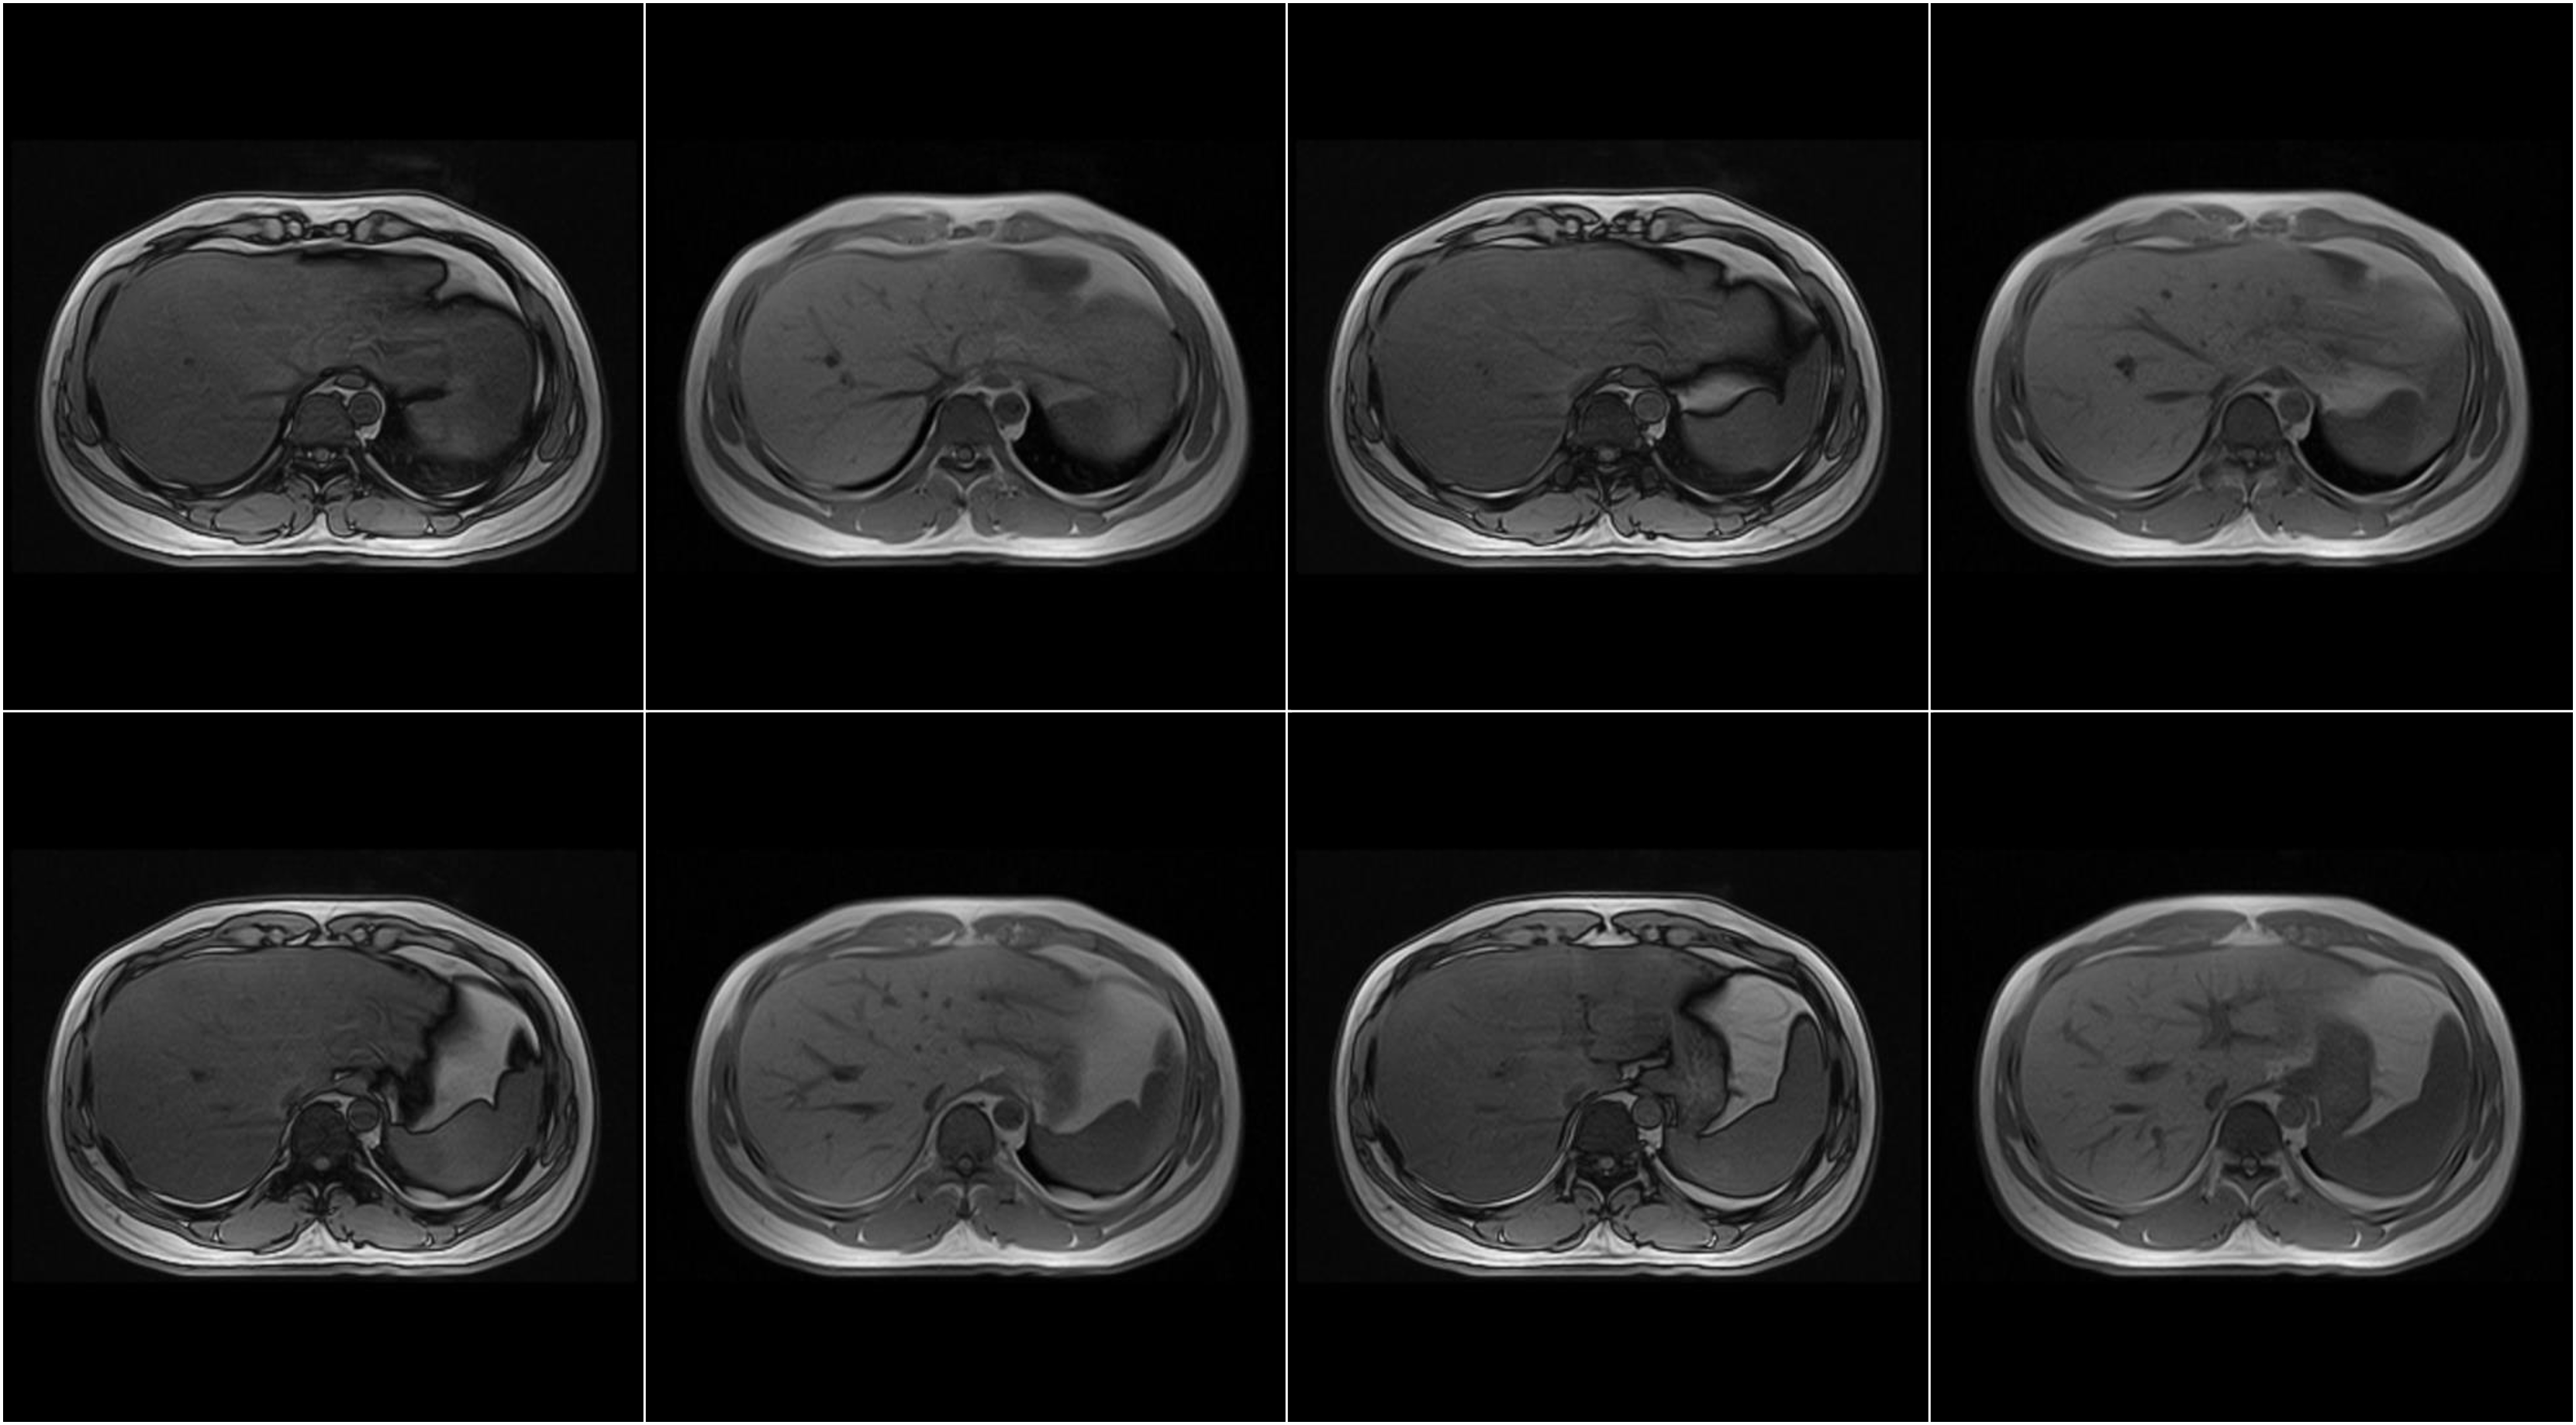

Hình ảnh lâm sàng